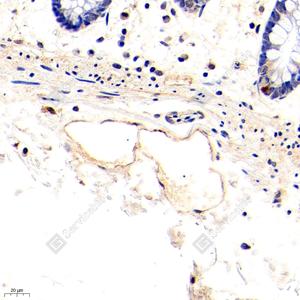

IHC检测LYVE1蛋白(货号 GB111689). 样品: 人小肠, 4%多聚甲醛 (货号G1101) 固定12-24小时. 抗原修复: 柠檬酸抗原修复液(干粉, pH 6.0) (G1201), 98℃, 20分钟. —抗: 1: 400稀释, 4℃ 孵育过夜. 二抗: HRP标记山羊抗兔IgG (H+L) (货号GB23303), 1: 200稀释, 室温孵育1小时. |